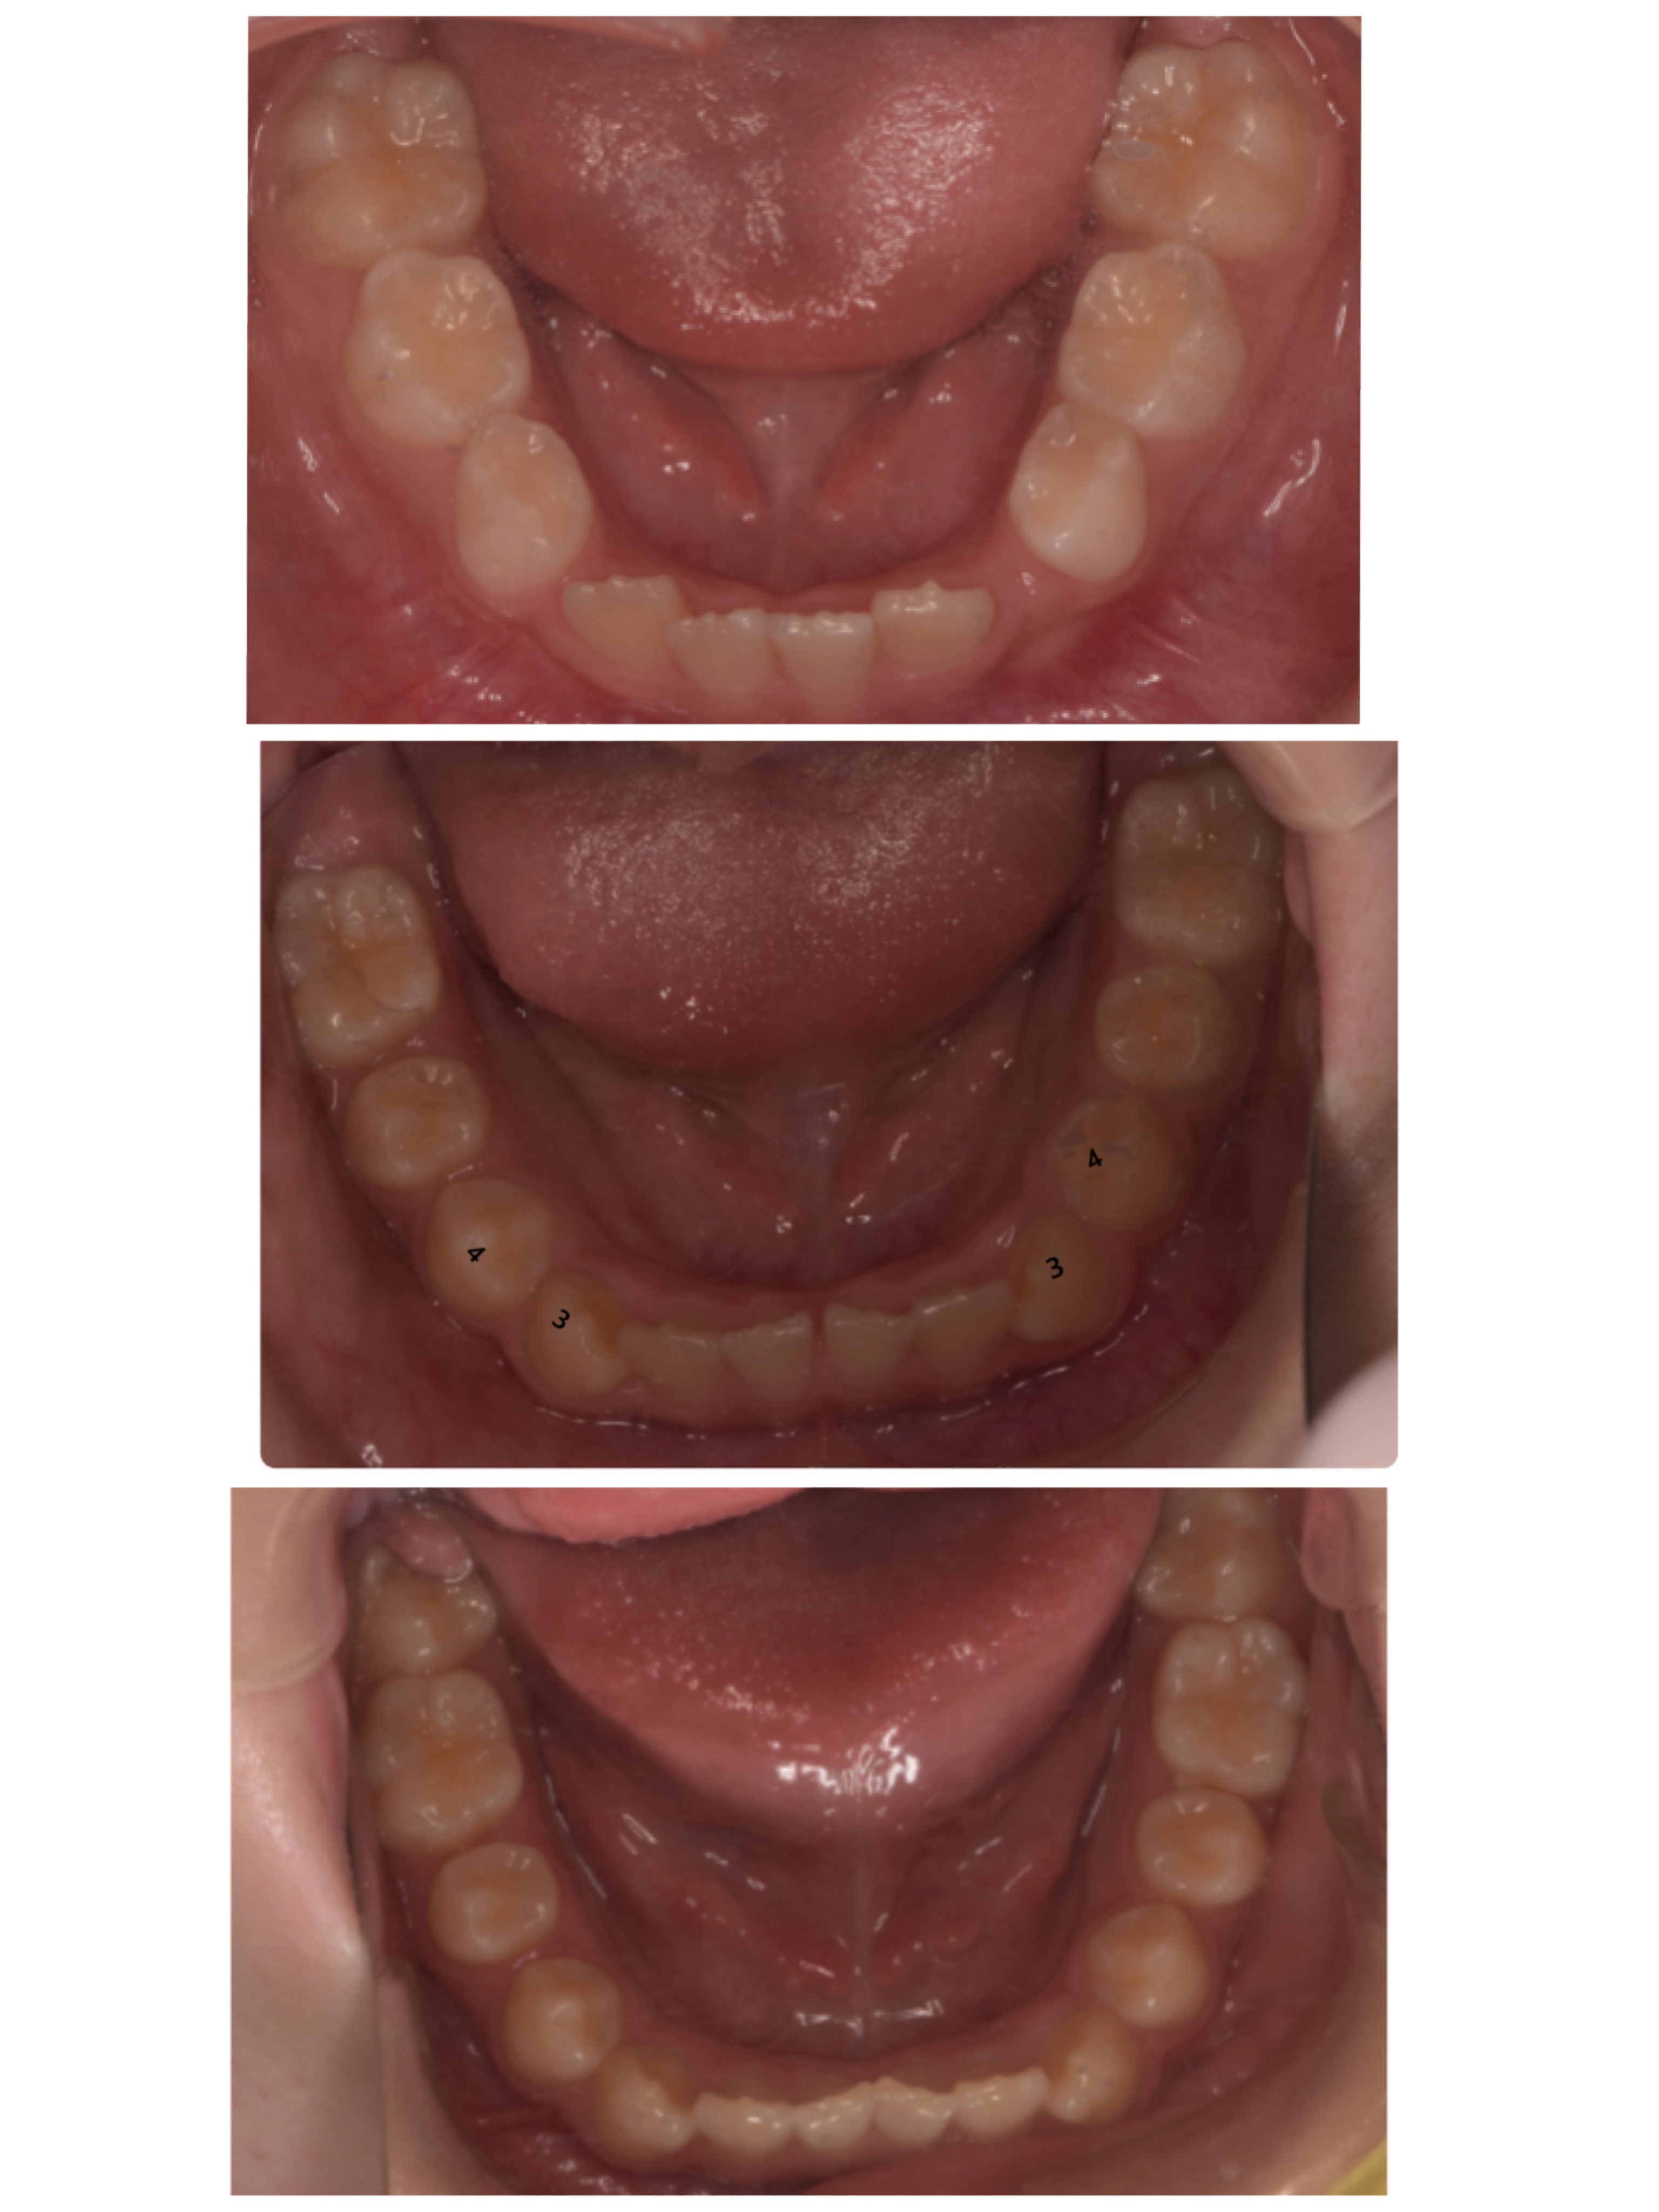

お口の中のお写真も見ていくとまだ下の歯は重なりがありますが、少しずつその重なりも少なくなって来ています。

歯と歯の間のスペースも少し広がって来ているのでもっと綺麗に並んでくれそうかな?と思います☺︎

お子様のプレート装置はブラケット矯正やマウスピース矯正とは少し違い、歯を直接動かすわけではなく顎のスペースを広げて並ぶようにする矯正装置なので少しずつ歯が並んでいくのを見守っていく形になります。